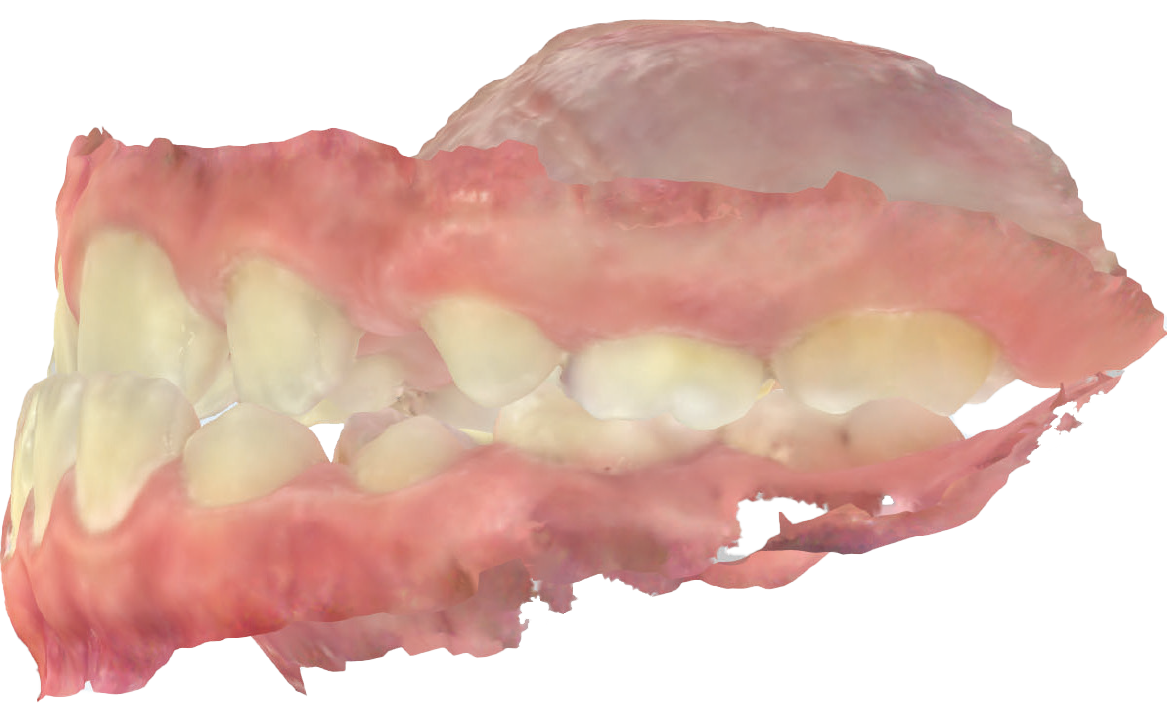

L’overjet e l’overbite sono entrambi ridotti in massima intercuspidazione. Trasversalmente il mascellare superiore è contratto (fig. 4-7).

Fig. 6B Modello digitale dell'arcata superiore.